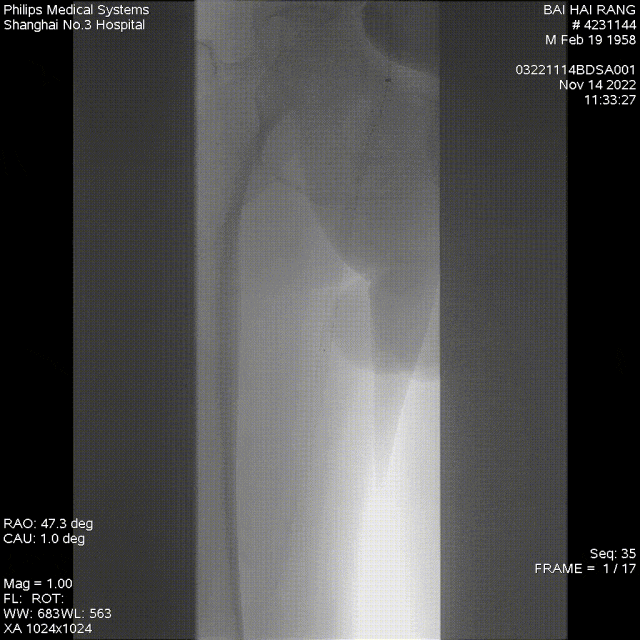

★ Case 1

noproximal stump in SFA,>250mm